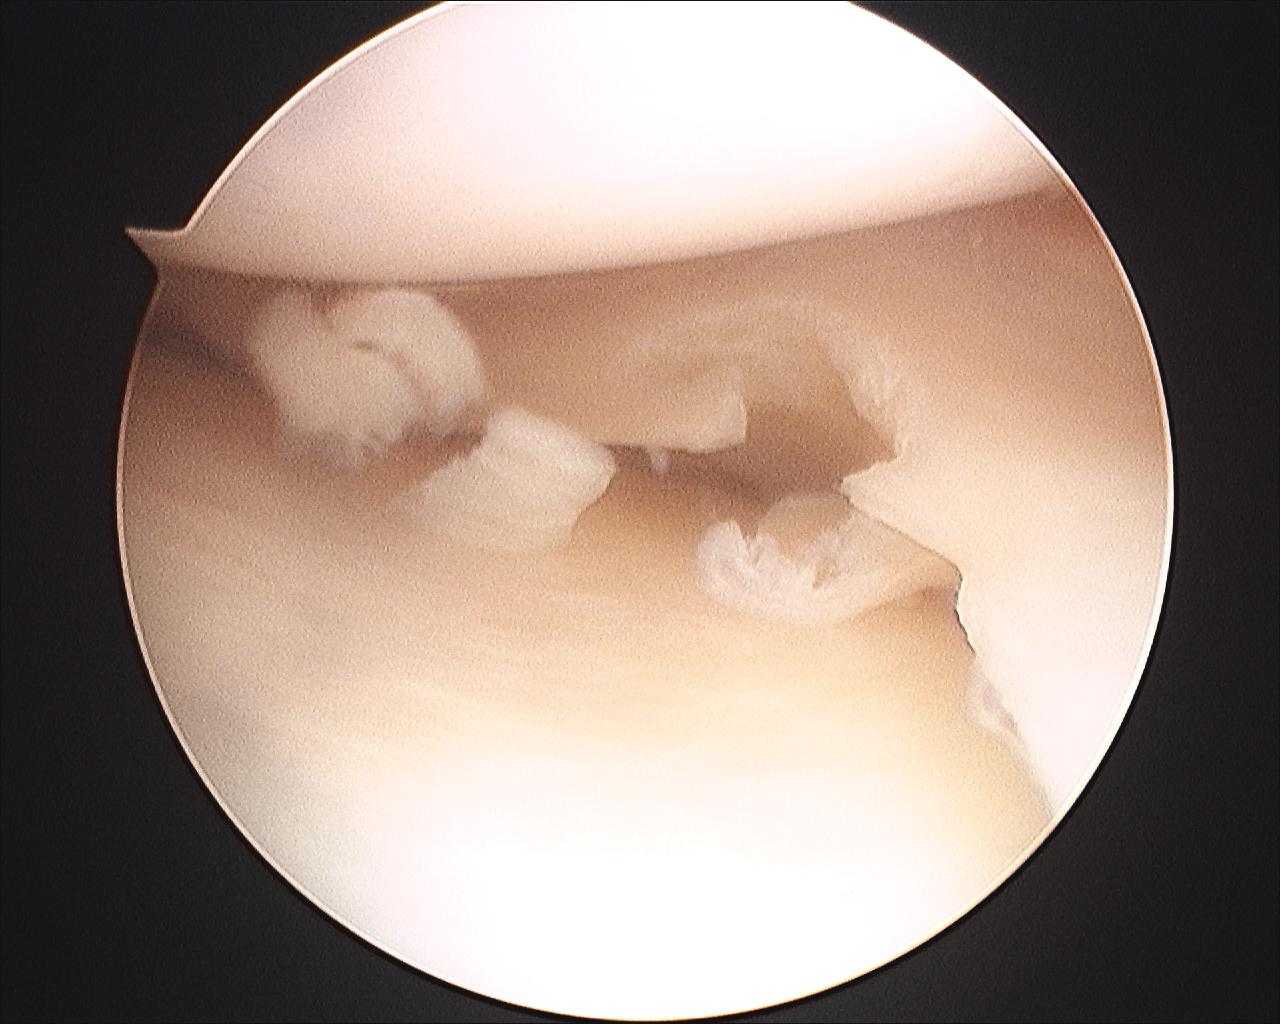

#menisco

Inter, lesione al menisco laterale per Medel: fuori almeno un mese

Confermata lesione del menisco, lungo stop per Storari

Lazio: sospetta lesione al menisco per De Vrij, crollano gli abbonamenti

Cellule staminali per un nuovo menisco